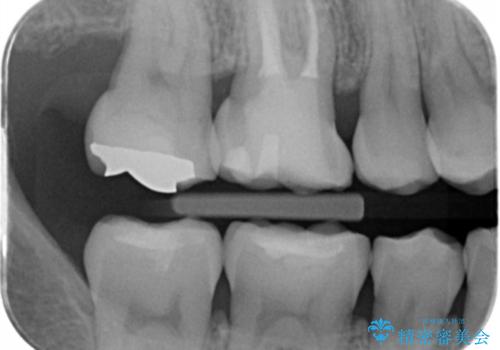

古い樹脂の劣化 セラミックインレー治療

- 保険診療での古い樹脂の劣化が気になるとの事で来院。

二つ樹脂の劣化が見られるので提案をしたが、まずは一つ治療を行いたいとの事でしたので拡大鏡下で劣化した樹脂と虫歯を取り除いた後e-maxインレーにて治療を行いました。

適合の良い詰め物が入りました。